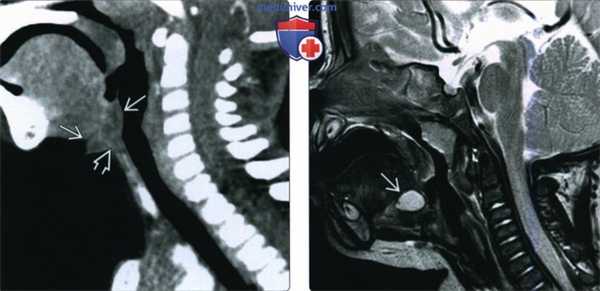

(Слева) На рисунке показан ход щитоязычного протока, начинающегося на уровне слепою отверстия и распространяющегося до ложа щитовидной железы. Обратите внимание, что проток вплотную прилежит к средней части подъязычной кости. Кисты могут возникать в любом месте по ходу протока.

(Справа) При сагиттальной КТ с КУ в корне языка по средней линии визуализируется объемное образование с ровными краями, выглядящее кистозным. Образование было случайно выявлено на КТ, выполненном с целью оценки распространенности инфекции глубоких тканей шеи (изменения не продемонстрированы), и впоследствии было верифицировано как киста щитоязычною протока. (Слева) При сагиттальной КТ с КУ у ребенка с жалобами на боль в горле и затруднение глотания в подъязычном пространстве по средней линии визуализируется гиподенсное объемное образование с фестончатыми краями, распространяющееся в сторону корня языка и в область валлекул. При морфологическом исследовании подтвердилась киста щитоязычного протока с признаками воспаления.

(Справа) На Т1ВИ в сагиттальной проекции у ребенка с рецидивом кисты щитоязычного протока в корне языка по средней линии визуализируется кистозное образование. Отмечается деформация языка и верхней части объемного образования, обусловленная ларингеальной маской, используемой для анестезии.

(Слева) При сагиттальной КТ с КУ у ребенка с рецидивирующей кистой щитоязычного протока в надподъязычном отделе шеи по средней линии визуализируется объемное образование неоднородной структуры с бугристыми краями, наличие которого позволяет предположить воспаление остатка щитоязычного протока. Обратите внимание, что средняя часть подъязычной кости отсутствует, что связано с ранее выполненной операцией Систранка.

(Справа) При сагиттальной МРТ Т2ВИ у ребенка, которому данное исследование было выполнено из-за судорожных припадков в корне языка по средней линии визуализируется случайно выявленное объемное образование с гиперинтенсивным сигналом, которое впоследствии было верифицировано как КЩЯП.